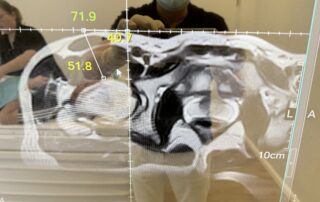

Nach ärztlicher Untersuchung und Aufklärung erfolgt die MRT-Untersuchung mit speziellen Sequenzen, welche wir nachfolgend zur genauen Navigationsplanung benötigen. Nach Festlegung der Navigationslinien auf dem Monitor sowie einer gründlichen Desinfektion der Einstichstelle erfolgt die eigentliche Injektion anhand der festgelegten Parameter (Abstand/Winkel und Tiefe) mit einer antimagnetischen Spezialnadel. Vor der Injektion wird ein weiterer kurzer MRT-Scan zur Überprüfung der Nadelposition durchgeführt, woraufhin das Präparat (z. B. PRP) oder Medikament (etwa bei der PRT) unter sterilen Kautelen präzise auf den Punkt injiziert wird.